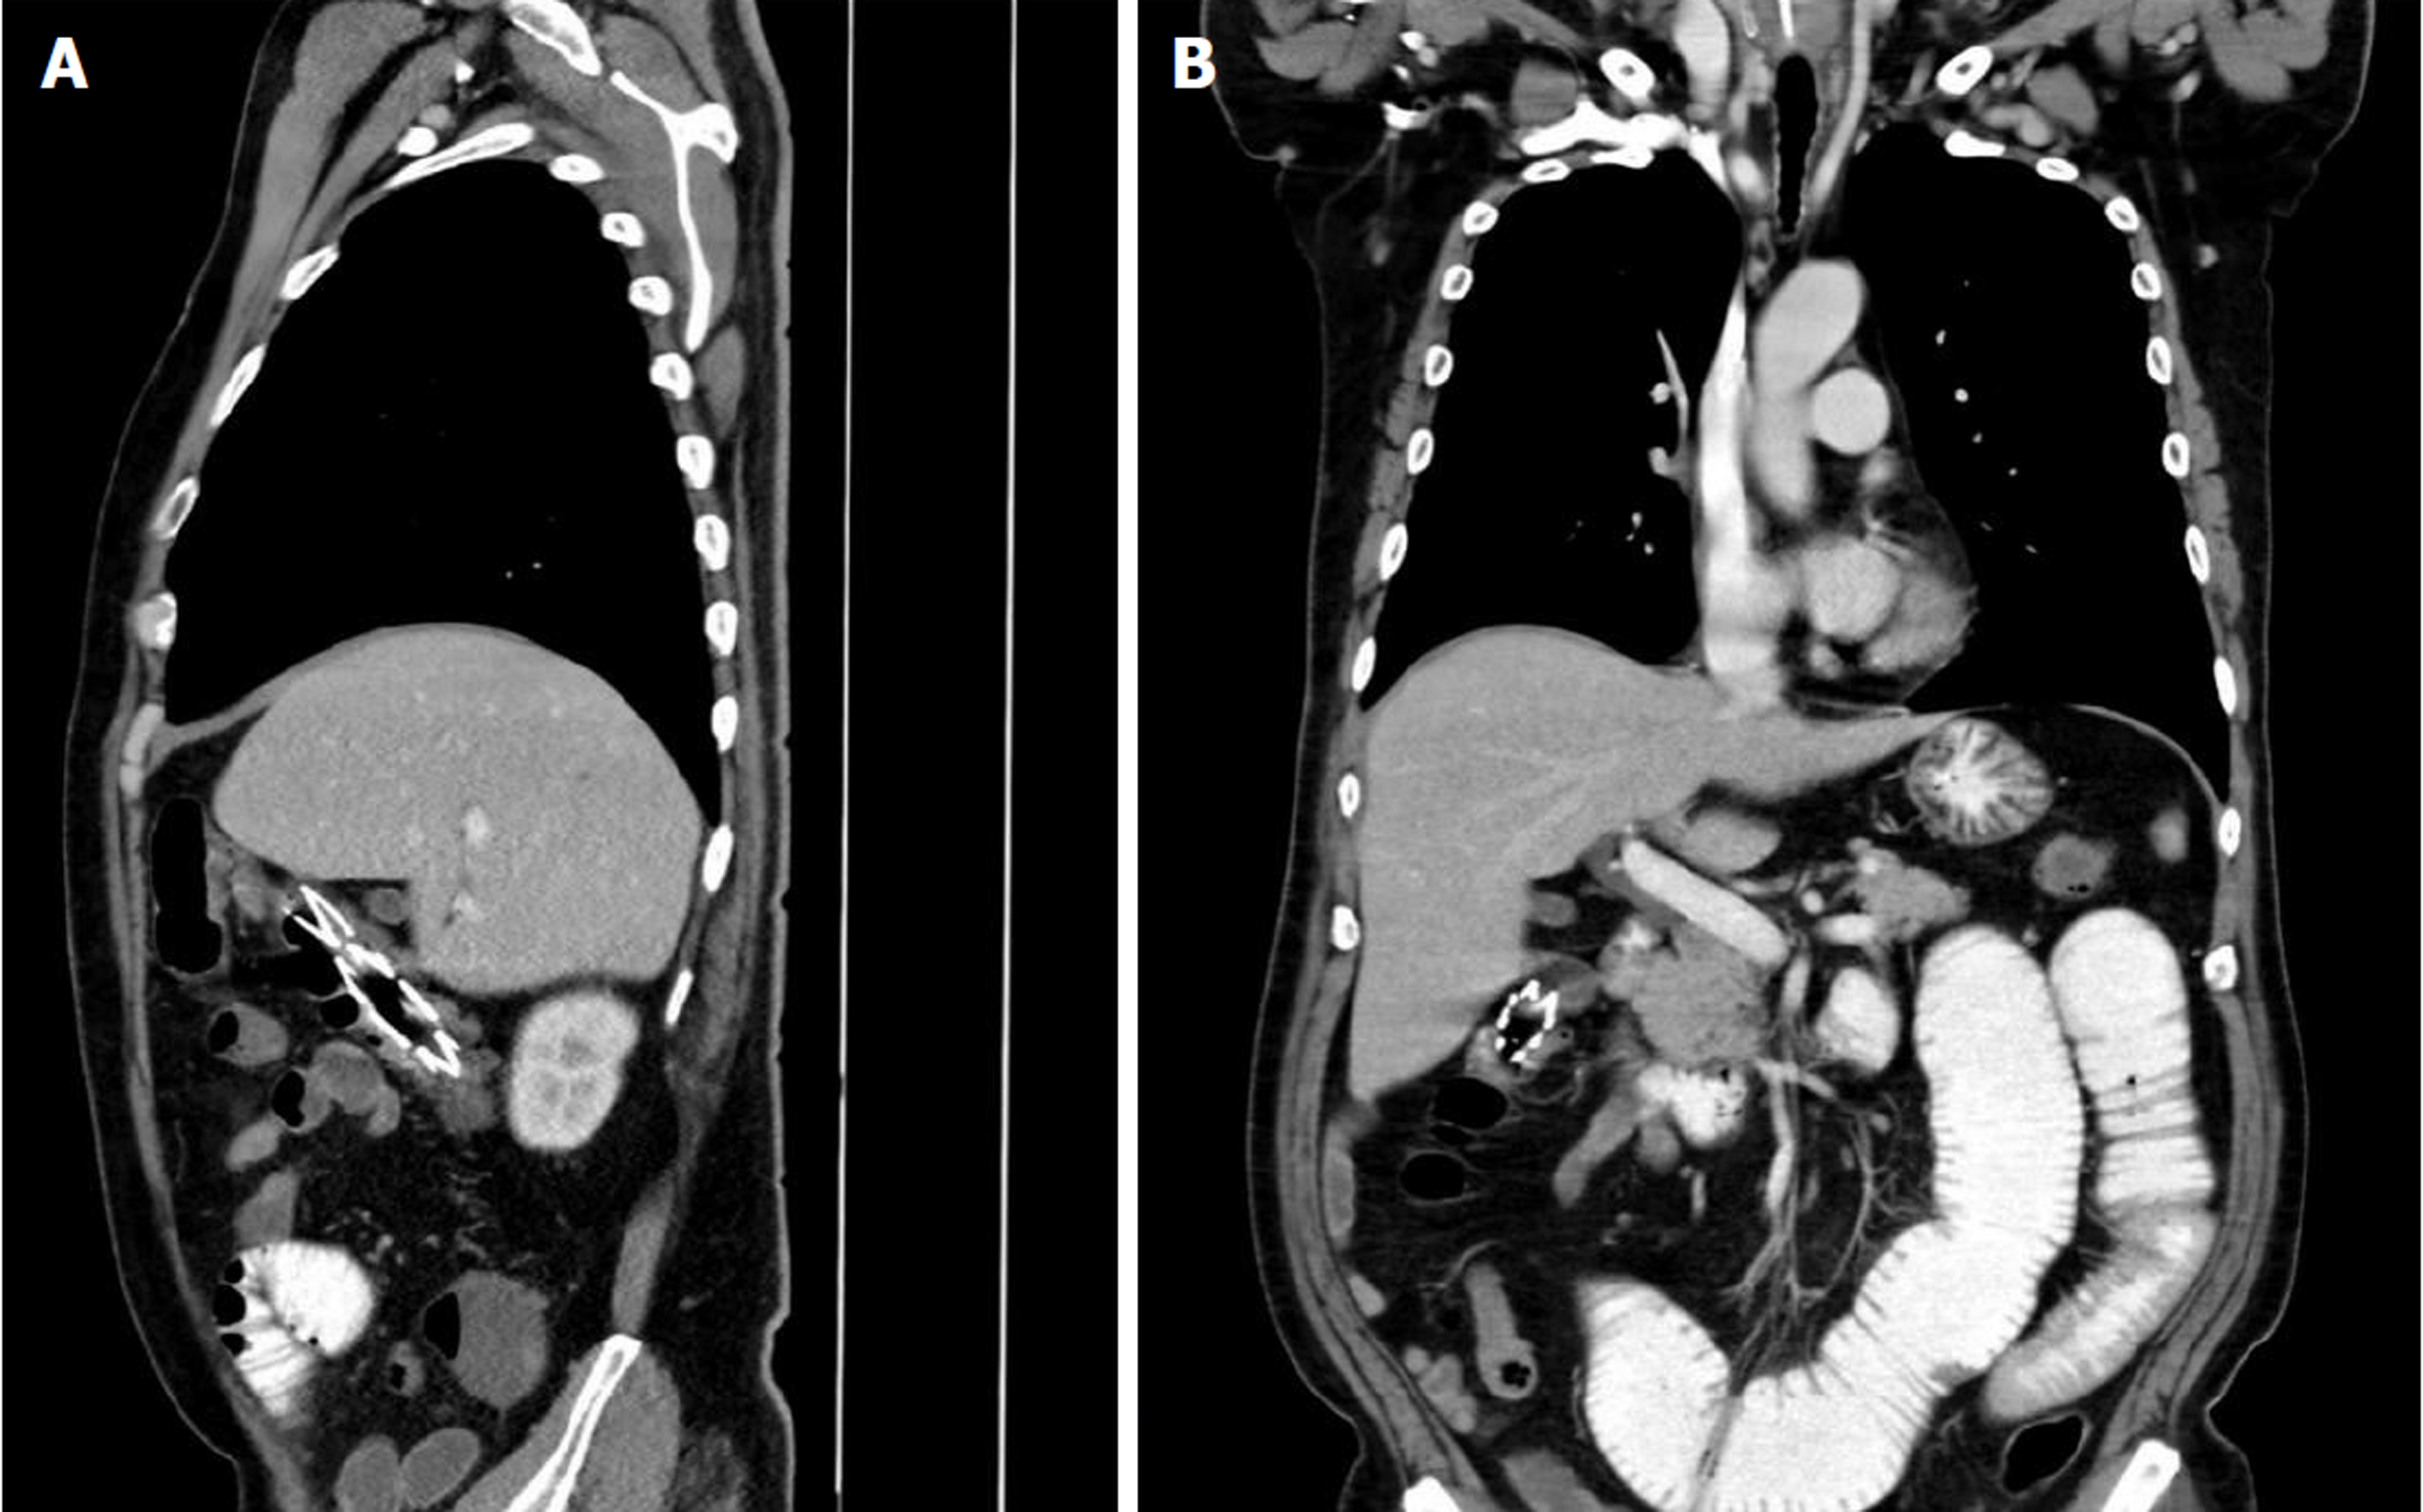

胸腹部电脑断层扫描(computed tomography, CT)(2025.1.1): 食管支架移位至升结肠伴局部梗阻, 有可疑肠穿孔. 复查胸腹部CT(2025.1.4): 食管支架移行至结肠肝曲, 升结肠近端靠回盲部可疑肠套叠, 管壁稍肿胀, 升结肠近端前方局部少许积气, 肠穿孔待排(图1).

本病例为一例食管癌支架置入术后1 mo余发生支架移位, 以脐周疼痛为主要症状就诊, 影像学证实支架移位至肠道并嵌顿于结肠肝曲, 临床上少见. 考虑患者行化疗及免疫治疗后肿瘤缩小, 导致支架与肿瘤嵌合不稳定而发生移位. 因嵌顿部位在右半结肠位置较远处, 肝曲的解剖位置导致该处曲度大, 食管长径支架移位于此后难以自行继续下移, 且CT提示有可疑肠穿孔, 行肠镜操作存在一定风险及难度, 尤其是无法钩住口侧端的可回收线从而将支架回缩收拢, 支架展开状态拖出容易造成肠壁的划伤, 甚至肠穿孔, 在操作前需要与患者及家属充分沟通内镜下取支架可能失败, 甚至急诊外科手术, 取得充分理解并签署知情同意书. 我们采用钳尖较为柔和的活检钳来夹取牵拉支架肛侧端, 轻柔、缓慢沿着肠腔纵轴将支架拖出, 以最大程度避免肠壁黏膜损伤, 虽耗时较长, 但最终顺利取出支架, 未造成肠壁明显受损, 避免外科手术创伤. 通过此病例, 我们有以下体会: (1)应根据病变位置, 选取合适材质、形态、直径及长度的食管支架; (2)向患者做好术后宣教, 支架置入后1-2 wk内以流质或半流质食物为主, 要少食多餐; 对置入记忆合金支架患者尤其注意术后禁忌冰冷食物以防支架变形脱落; (3)出现再次进食梗阻、腹痛等情况, 需警惕支架移位, 尽早来医院就诊; (4)对发生移位的支架可采用内镜下复位或移除支架, 支架上缘进行内固定、外固定等方法来预防移位, 保守观察或内镜下无法移除者必要时采取外科手术治疗; 和(5)既往多采用圈套器、异物钳取消化道异物, 在个体情况下也可酌情使用活检钳来进行此操作.